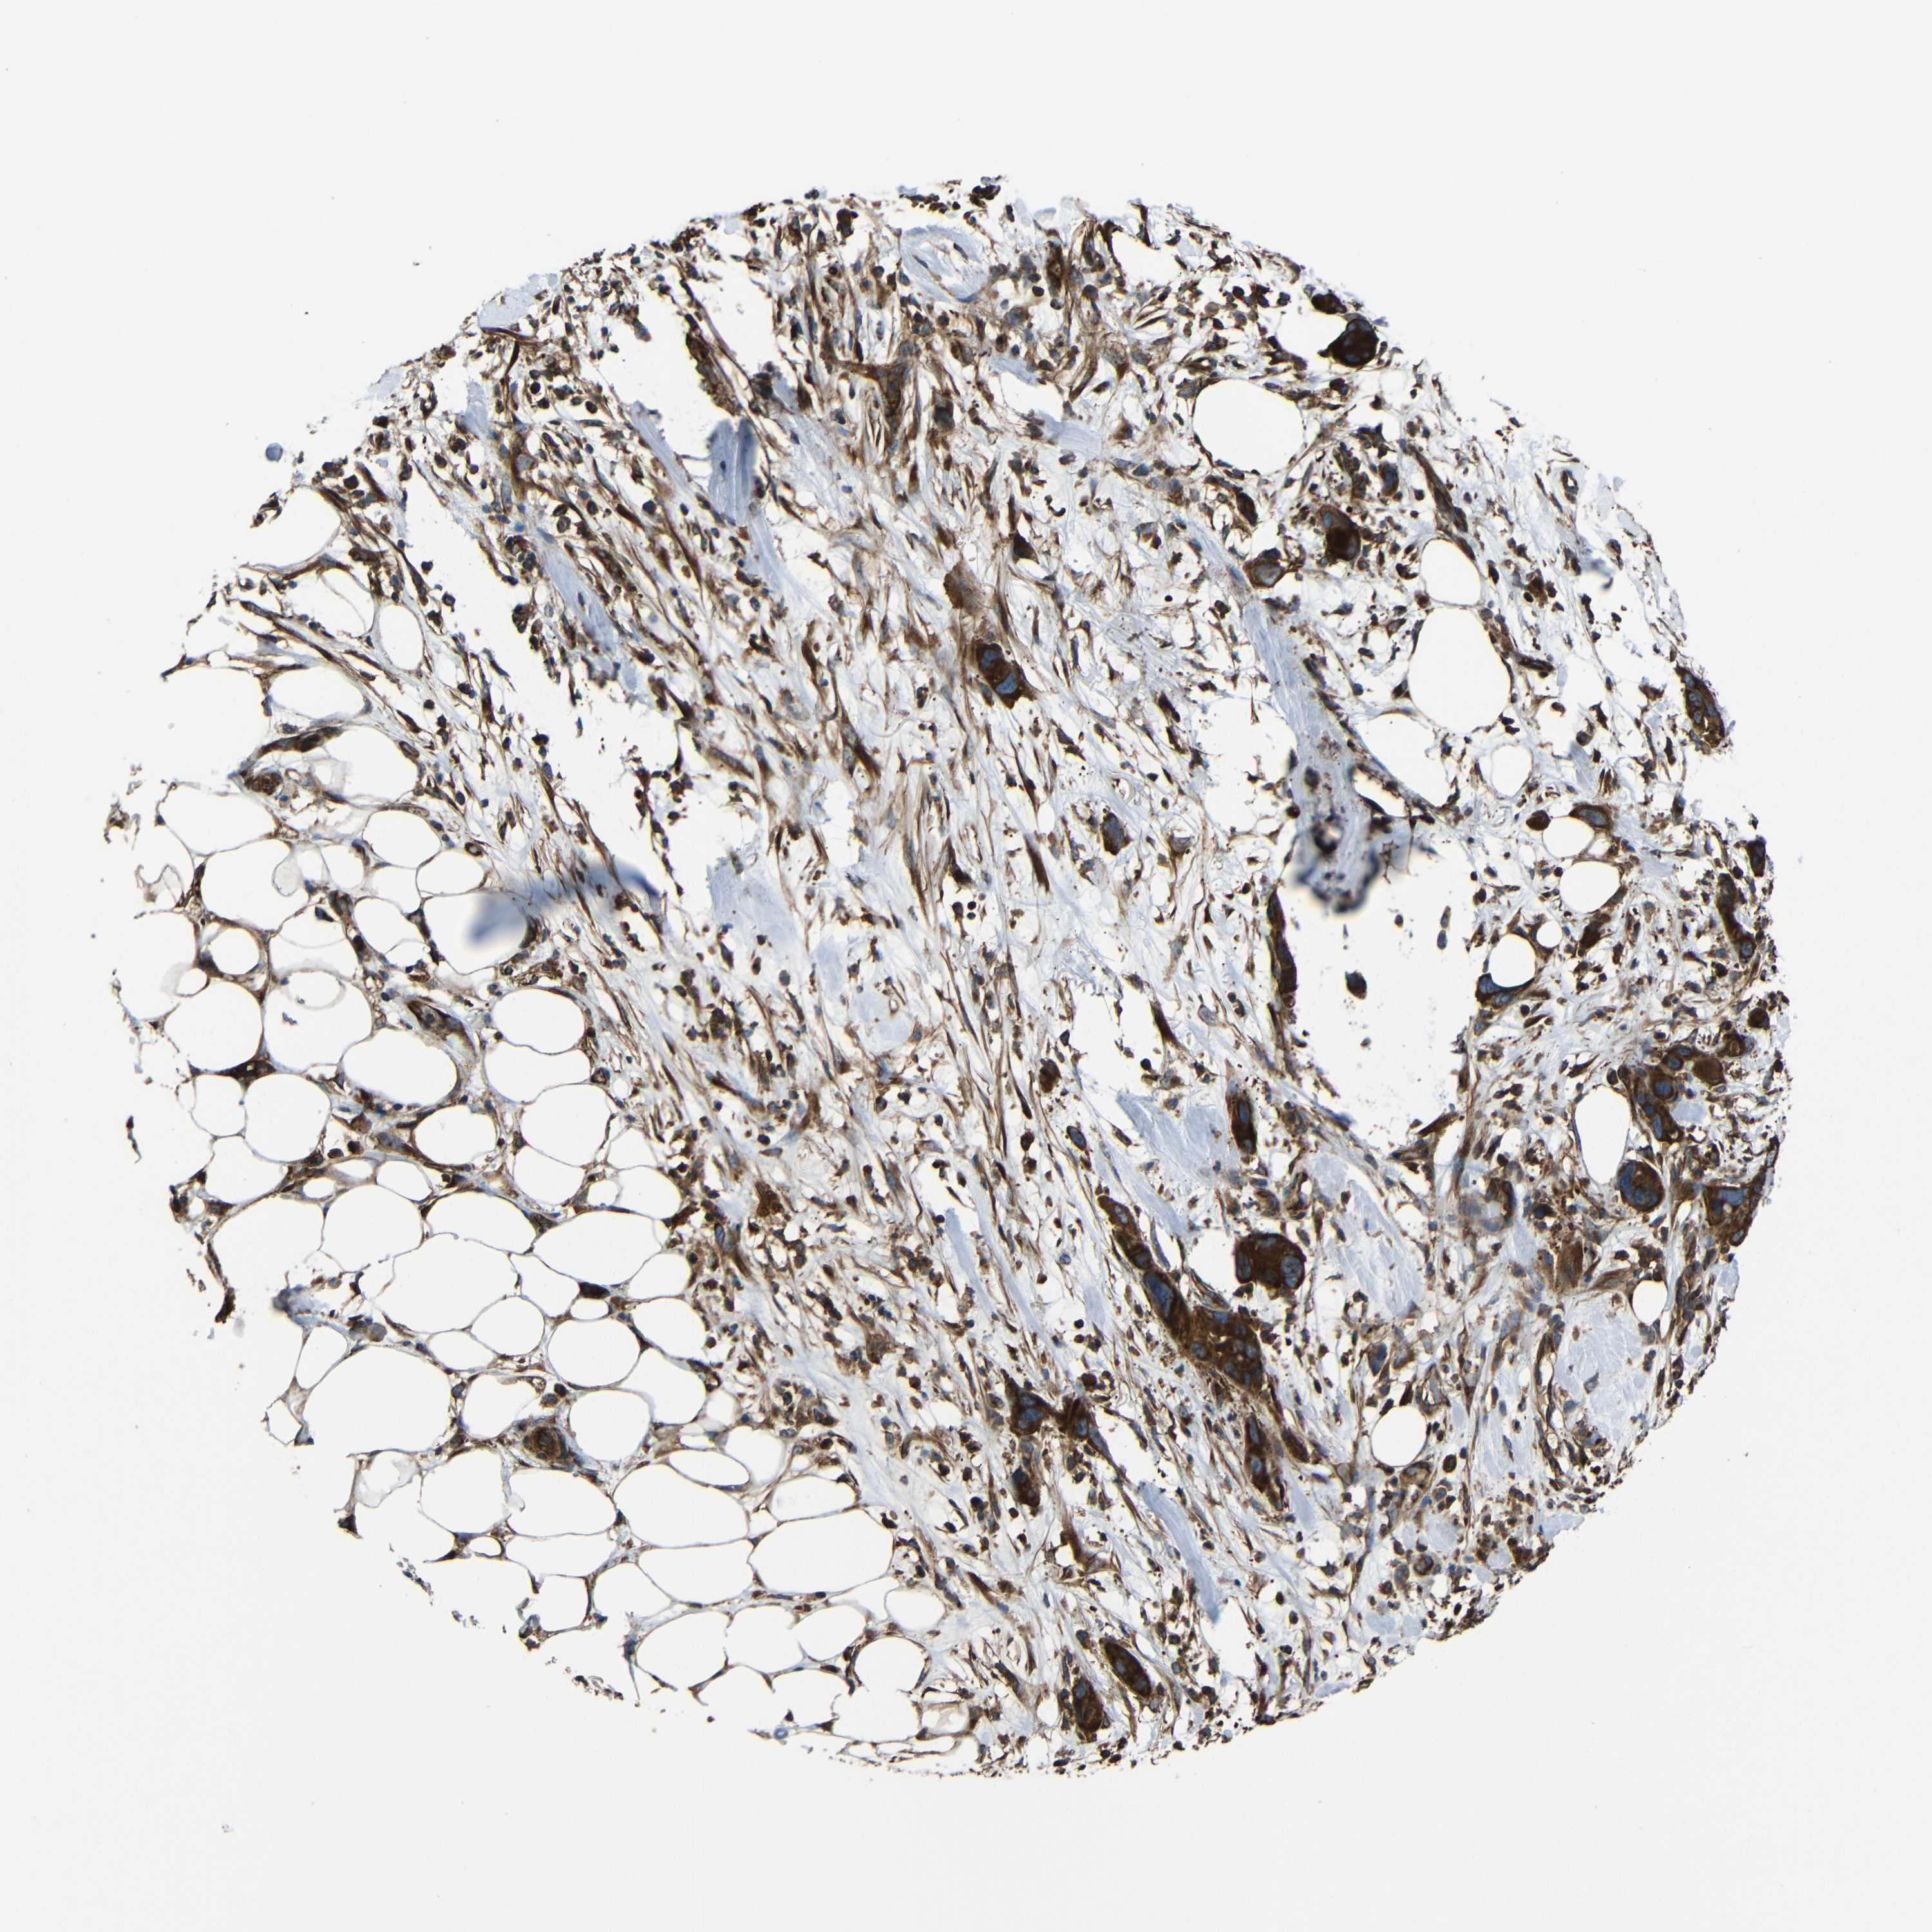

PANCREATIC CANCER - Protein expressioni

A mouse-over function shows sample information and annotation data. Click on an image to view it in a full screen mode. Samples can be filtered based on level of antibody staining by selecting one or several of the following categories: high, medium, low and not detected. The assay and annotation is described here.

Note that samples used for immunohistochemistry by the Human Protein Atlas do not correspond to samples in the TCGA dataset.

Antibody stainingi

Antibody staining in the annotated cell types in the current human tissue is reported as not detected, low, medium, or high, based on conventional immunohistochemistry profiling in selected tissues. This score is based on the combination of the staining intensity and fraction of stained cells.

Each image is clickable and will lead to virtual microscopy that enables deeper exploration of all samples and also displays staining intensity scores, fraction scores and subcellular localization as well as patient and tissue information for each sample.

Antibody CAB013717

Staining

High

Medium

Low

Not detected

Intensity

Strong

Moderate

Weak

Negative

Quantity

>75%

75%-25%

<25%

None

Location

Nuclear

Cytoplasmic/membranous

Cytoplasmic/membranous,nuclear

Adenocarcinoma, NOS